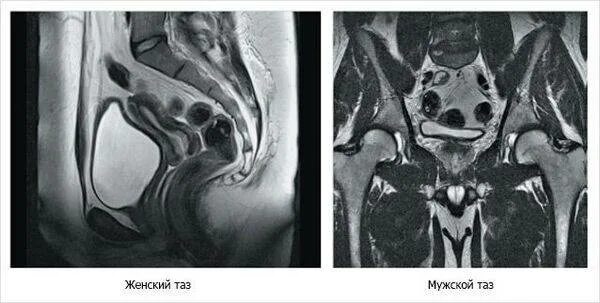

Можно ли сделать мрт малого таза